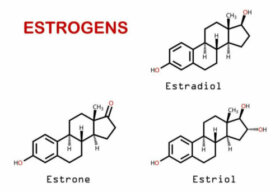

두통은 호르몬 불균형을 포함한 여러 몸 상태에 따라 흔히 나타나는 증상이다. 감기, 안과 질환 등 거의 모든 질환이 두통을 유발하는데 이번 글에서는 호르몬과 두통 사이의 관계를 이야기해 보려고 한다. 대부분 호르몬 불균형에 크게 신경 쓰지 않지만 호르몬 불균형은 특히 여성에게…